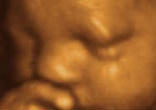

Lord, To Whom Shall We Go? The Ultrasound Generation